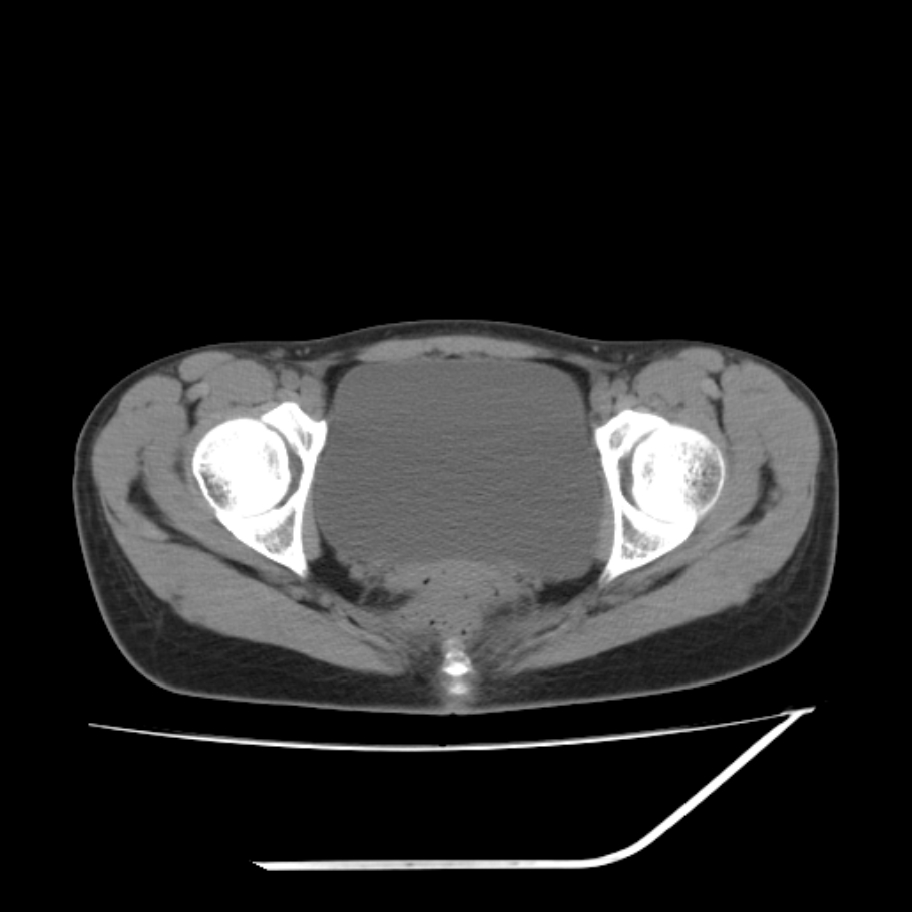

女,25岁。偶尔有右下腹不适感,余无明显异常。(结婚半年),囊壁较厚,是卵巢囊肿吗?

右侧卵巢区椭圆形囊性肿物,内壁光滑 无分隔。直肠子宫间隙内有少量积液征象。结合临床考虑卵巢巧克力囊肿,还要问问有没有痛经,本例ct怎么没有灌肠?要是灌肠或前一前口服造影剂,起码可以和肠管区别开

右侧囊性占位,1囊肿,2囊腺瘤。

考虑右侧卵巢囊性占位性病变(巧克力囊肿?),盆腔积液有不排除宫外孕可能,请结合临床和b超。